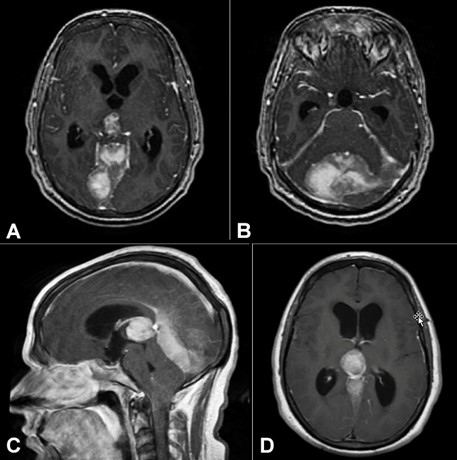

In the Emergency Department, the patient was vitally stable. The complete blood count and complete metabolic panel were unremarkable, chest x-ray, urine analysis and blood cultures did not show infection. A neurological exam was significant for decreased active range of motion of the cervical spine with pain on palpation of the right trapezius but no appreciable erythema or mass. The exam was negative for focal weakness or paresthesia, and deep tendon reflexes were 2+. Magnetic resonance imaging (MRI) with and without IV contrast showed multiple heterogeneous intracranial masses with resultant mass effect compressing the cerebral aqueduct with dilation of the 3rd and 4th ventricles hydrocephalus and tonsillar herniation (Figure 1).